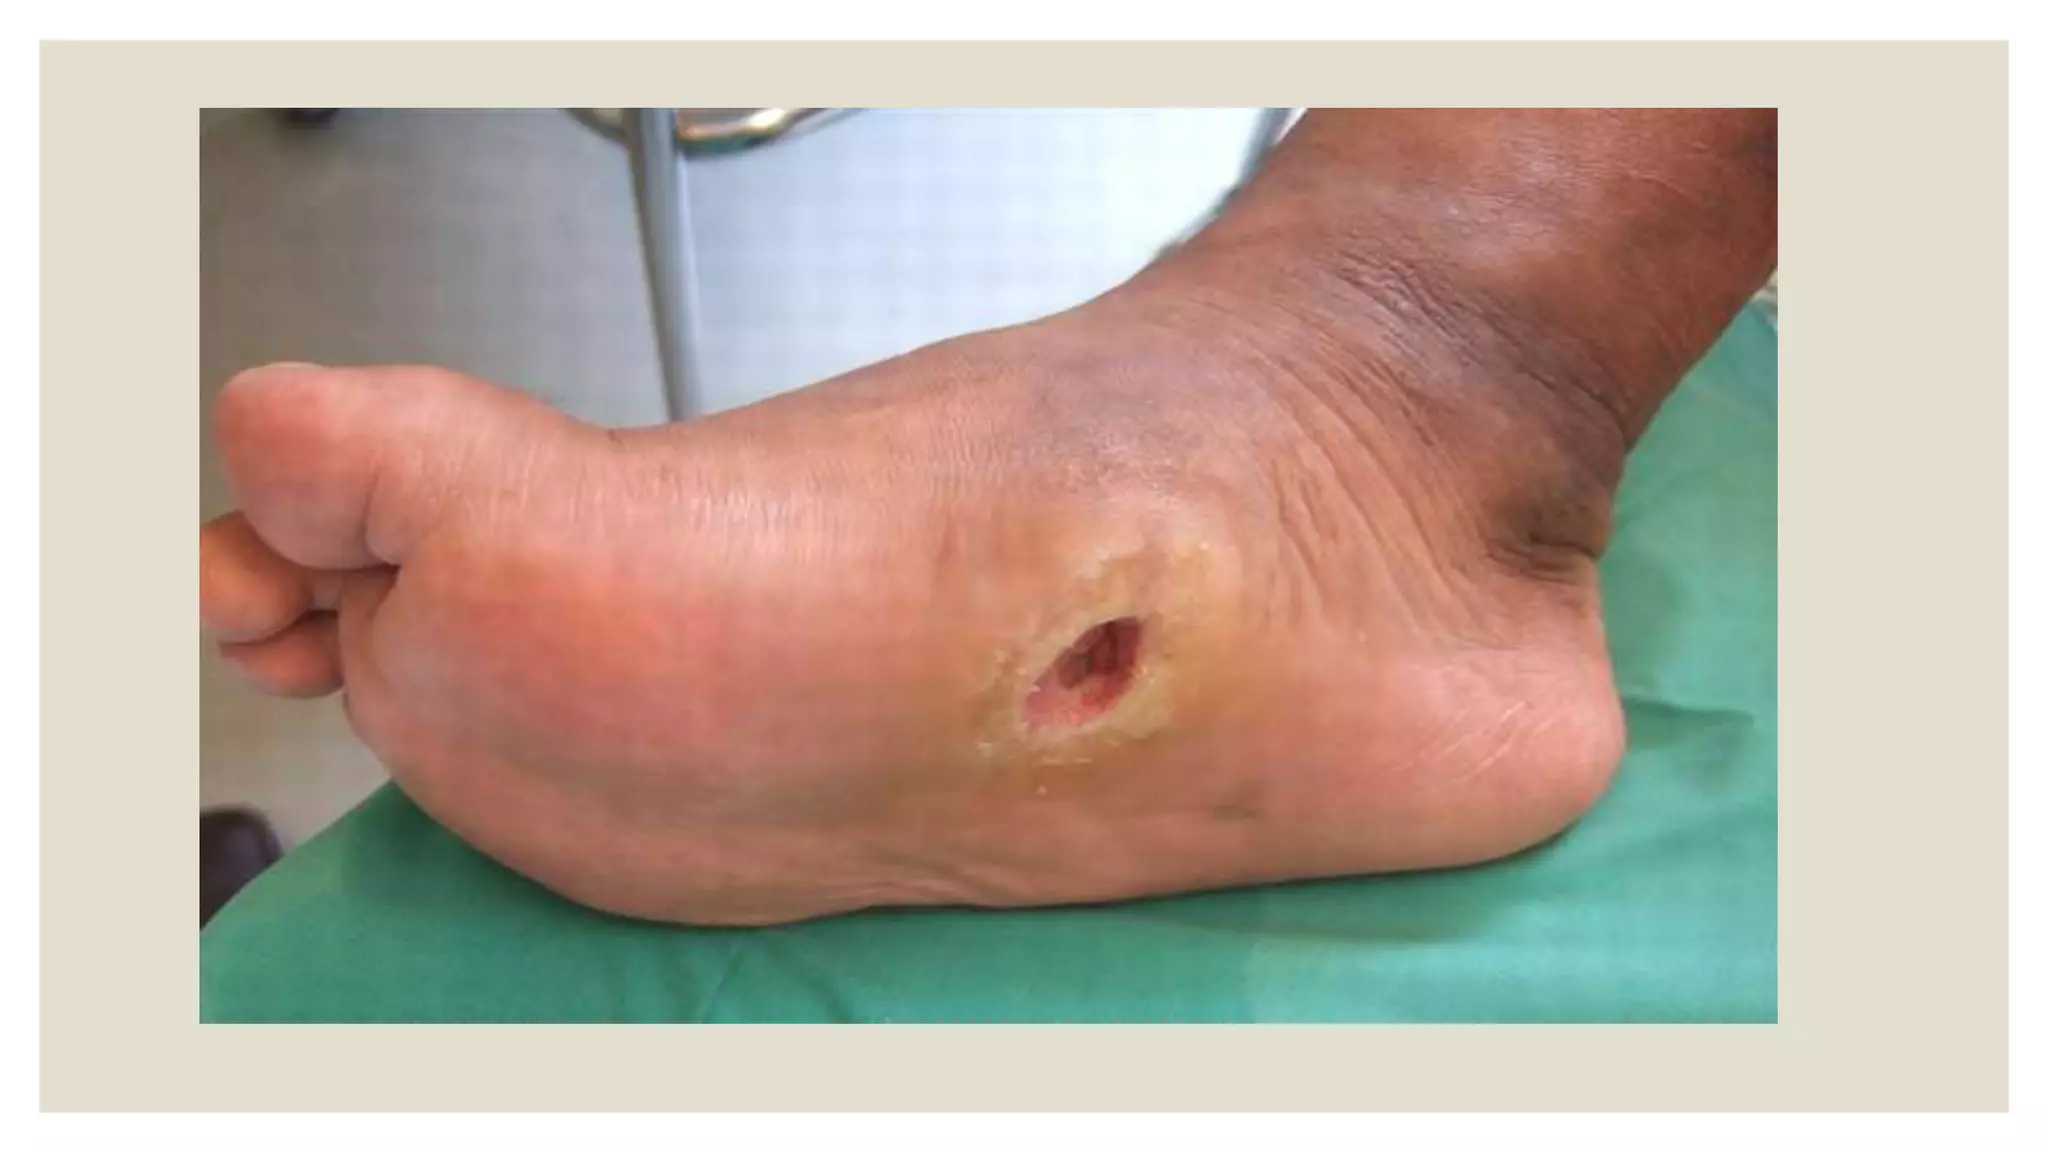

-skin changes in LLs : trophic ulcers , brittle nails , thin skin , coldness

Diabetic polyneuropathy

◦ D.M., is one of the most common causes of disabling polyneuropathy world wide .

◦ Length dependant diabetic Polyneuropathy.

◦ More than 80% of patients with clinical diabetic neuropathy have the distal

symmetrical form of the disorder.

Neuropathy may be the 1st symptom of D.M.

◦ Patterns of DPN:

-Diabetic sensori-motor neuropathy.

- Diabetic autonomic neuropathy.

- Diabetic proximal neuropathy.

- Diabetic mononeuropathy (cranial or peripheral)

- Diabetic trunkal neuropathy.

The same patient may develop two or more of these types.

Management :

1- Strict control of blood sugar.

2- Aldose reductase inhibitors " sorbinol"

3- Vasodilators and tonics.

4- Carbamazepine, gabapentin, amitriptyline, duloxetine may help in sensory

discomfort.

5- Skin care is very essential.